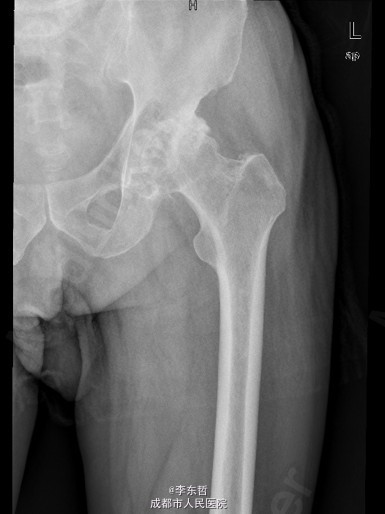

患者男,76岁,因“外伤致左髋部疼痛40多年,加重伴跛行2年”入院;患者自诉40多年前因一次摔伤致左髋关节脱位,给予手法复位后治愈,以后时有疼痛,关节活动好,不影响行走,4年前出现左髋部疼痛加重,活动后明显,休息后缓解,无腰腿痛,无肢体麻木等不适,给予对症治疗,稍有好转,以后反复发作,长时间行走后疼痛明显加重,2年前出现左下肢无力,长距离行走后出现跛行,且左髋关节有异响感;2月前出现左髋部疼痛加重,行走时尤为明显,步行约500米即出现疼痛,伴跛行,偶有静息痛;以后反复出现左髋部疼痛,并逐渐加重,严重影响日常生活;1月前于当地医院摄片提示左股骨头坏死,为求进一步治疗,遂来我院,门诊以“左髋骨关节炎”收入住院。 患者自患病以来精神、饮食、睡眠可,二便正常,体重无明显变化。

查体:左侧腹股沟中点深压痛,左髋部伴有轴向叩击痛,双下肢感觉正常,双足背动脉搏动良好。左下肢较右下肢短缩约2cm;左髋屈65°,伸0°,内收10°,外展20°,内旋5°,外旋10°,左髋活动受限,内外旋诱发疼痛;Thommas征阴性,“4”字试验阳性;左下肢肌力正常,活动良好,右侧正常 ;辅助检查:X片示:左侧股骨头塌陷、密度增高,股骨头坏死可能,左髋骨质疏松.。